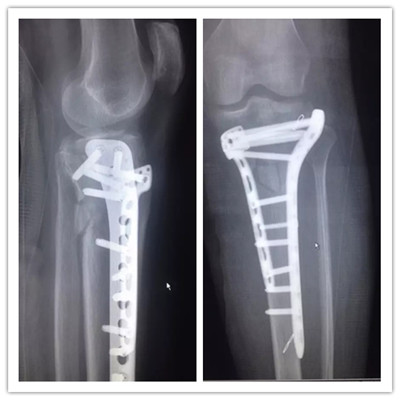

病例一:

患者小吳(化名),因車禍致左膝部受傷到廣安醫(yī)院就診,被診斷為“左脛骨平臺粉碎性骨折”,分屬第Ⅴ型,骨折移位明顯,碎裂嚴重,手術(shù)操作難度很大,殘留后遺癥幾率極高。廣安醫(yī)院院長劉志安通過“3D打印”進行“提前干預”,術(shù)前對鋼板放置的位置、數(shù)量及確定螺釘?shù)姆较蚝烷L度等,經(jīng)過反復多次的模擬手術(shù),評估不同的手術(shù)方法,討論手術(shù)策略,制定出最適宜的個性化手術(shù)方案。

3D打印效果圖